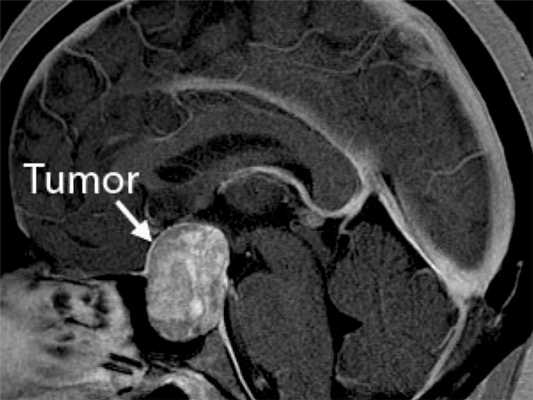

Опухоль головного мозга на МРТ

Опухоль мозжечка на МРТ (указана стрелкой)

Опухоли головного мозга долгое время диагностировали исключительно по клиническим признакам, часто слишком поздно. С появлением нейровизуализационных методов стало возможным выявление опасных патологий на ранних этапах их развития. Уже на первых стадиях формирования опухоль головного мозга на МРТ отчетливо видна, а врачи могут планировать дальнейшие действия. Ранняя диагностика увеличивает шансы на выздоровление даже при онкологических заболеваниях.